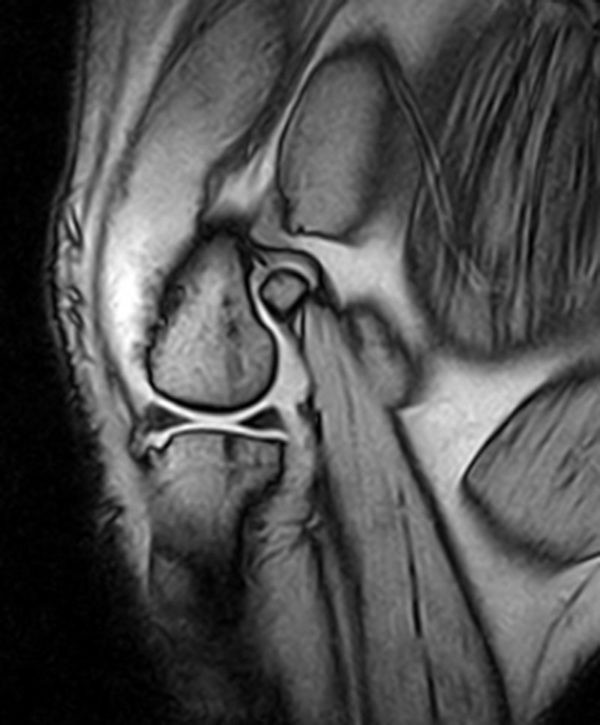

MRI image of a dog's left stifle.

Dog left stifle

MRI of the brain is often used to evaluate and define tumour types, infection, seizure disorders, strokes, hydrocephalus and other damage as a result of trauma. MRI of the spine is used for diagnoses of spinal cord tumours or syrinx, herniated disks, spinal cord compression and cord inflammation. Knee and hip MRI can be used to investigate tendon or ligament tears, bone or muscle tumours and inflammation.